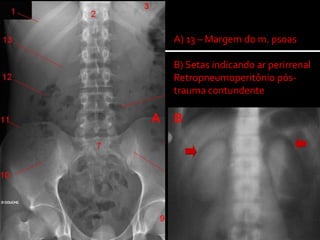

 Raio X simples de abdome, em posição supina:

 Retropneumoperitônio: definição de rins

ausência sombra m. psoas

 Hematoma retroperitoneal: ausência sombra m. psoas

 Fraturas ósseas – lesão órgãos adjacentes

 Corpos estranhos

A) 13 – Margem do m. psoas

B) Setas indicando ar perirrenal

Retropneumoperitônio pós-

trauma contundente

A B